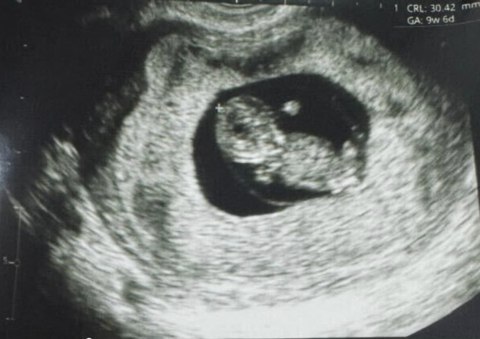

Репродуктивна медицина зробила історичний крок уперед: у Перу вперше народилася дитина, зачата за допомогою новітньої технології Fertilo, яка використовує стовбурові клітини для дозрівання яйцеклітини поза організмом.

Це відкриття стало можливим завдяки роботі біотехнологічної компанії Gameto, повідомляє New Atlas, передає Час Пік.